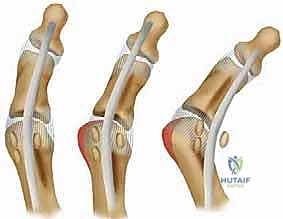

هنا يبرز سؤال هام: هل يتم استئصال العظمة السمسمية المكسورة (Sesamoidectomy) أم تثبيتها (Internal Fixation)؟

تاريخياً، كان الاستئصال هو الحل الشائع. لكن الأستاذ الدكتور محمد هطيف يتبنى المدرسة الحديثة التي تؤكد على ضرورة الحفاظ على العظمة السمسمية متى ما كان ذلك ممكناً عبر التثبيت الداخلي. استئصال العظمة يؤدي إلى خلل دائم في ميكانيكا القدم، يضعف قوة الإبهام بنسبة تصل إلى 30%، ويزيد من خطر تشوه إصبع القدم المطرقية (Cock-up toe deformity).

تُعد جراحة التثبيت الداخلي للعظم السمسمي (Internal Fixation of Sesamoid Bone) واحدة من أدق وأعقد جراحات القدم، وتتطلب جراحاً متمرساً في الجراحة المجهرية مثل الأستاذ الدكتور محمد هطيف. الهدف من الجراحة هو إعادة شظايا العظم إلى مكانها التشريحي الدقيق وتثبيتها ميكانيكياً لتسهيل الالتئام الطبيعي، مع الحفاظ على الأنسجة الرخوة المحيطة.